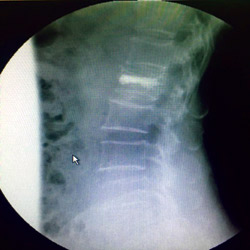

نجح المستشفى السعودي الألماني بالرياض مؤخراً في علاج مريضة في السبعين من عمرها، باستخدام الحقن الأسمنتي للفقرات، كانت تعاني من كسر انضغاطي في الفقرة القطنية ناتج عن هشاشة العظام لديها.

وكان المستشفى استقبل المريضة السبعينية التي كانت تتألم من وجود كسر في الفقرات القطنية، وتم عرضها على د.حازم فريد جراح العمود الفقري الذي وجَّه بعمل الفحوصات اللازمة، والتي أظهرت وجود هشاشة بالعظام، وعلى الفور تم التدخل الجراحي لعمل حقن أسمنتي للفقرة المنضغطة بعد رد الانضغاط؛ وذلك من خلال جرح صغير جداً لا يتعدى 1 سم وعلى أثرها غادرت المريضة في نفس اليوم بعد عدة ساعات من إتمام الجراحة وهي بحالة جيدة جداً مع تحسّن ملحوظ بألم الفقرات.